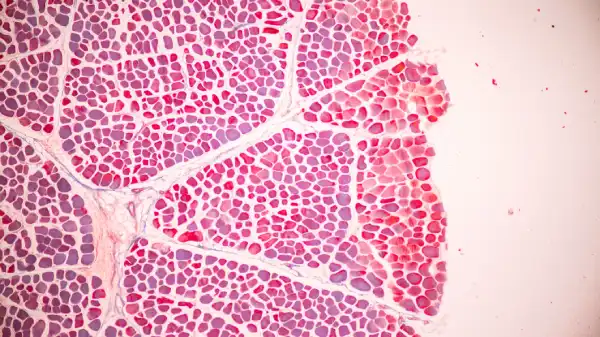

Tay-Sachs Disease

The availability of jscreen is a promising step in building upon the initial success of Tay-Sachs screening. Traditionally, Tay Sachs carrier screening required blood enzyme testing, but today’s sequencing method allows highly accurate testing to be performed on saliva. (In a small percentage of cases, blood enzyme testing will be needed in addition to saliva testing. A JScreen genetic counselor will notify you if that is the case, and help you arrange to have this performed.)